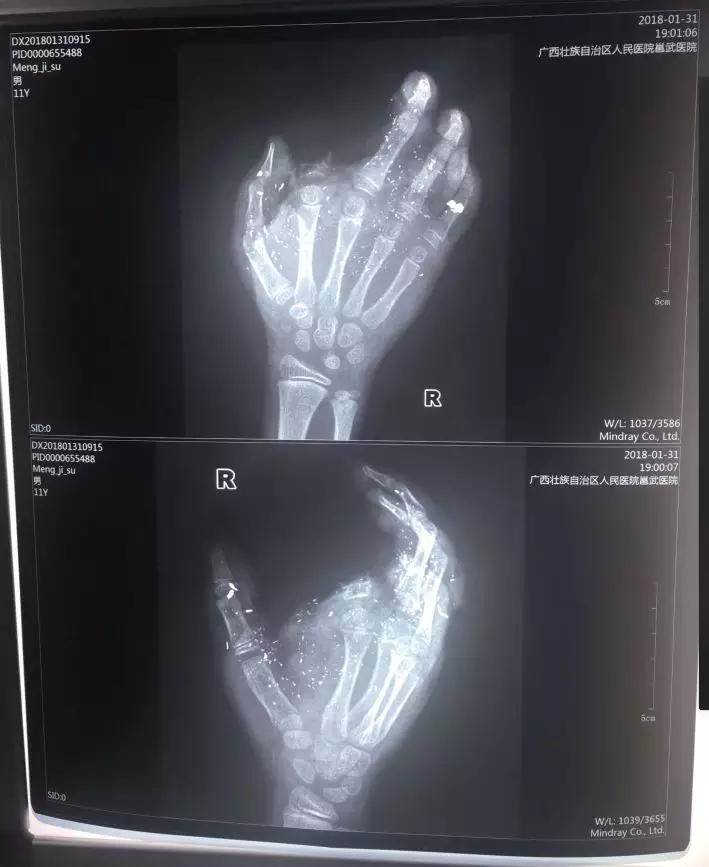

孩子送來醫院時傷勢很重。右手食指被炸沒了,拇指、中指、無名指也都炸傷,失去了供血,手掌皮膚被炸得稀爛。經CT檢查,右眼內有2塊手機碎片。

經過緊急的聯合會診,專家們認為孩子的手傷勢更緊急,必須立即手術,否則就喪失再植的機會了。

醫生于當晚12時連夜給孩子做手術,直到次日凌晨5時手術才完成。

記者從醫院了解到,孩子斷的那根手指已經植不回去了。目前手術通過血管移植,讓孩子損傷的另外3個手指恢復了血供,預計今后不會對功能造成太大影響。